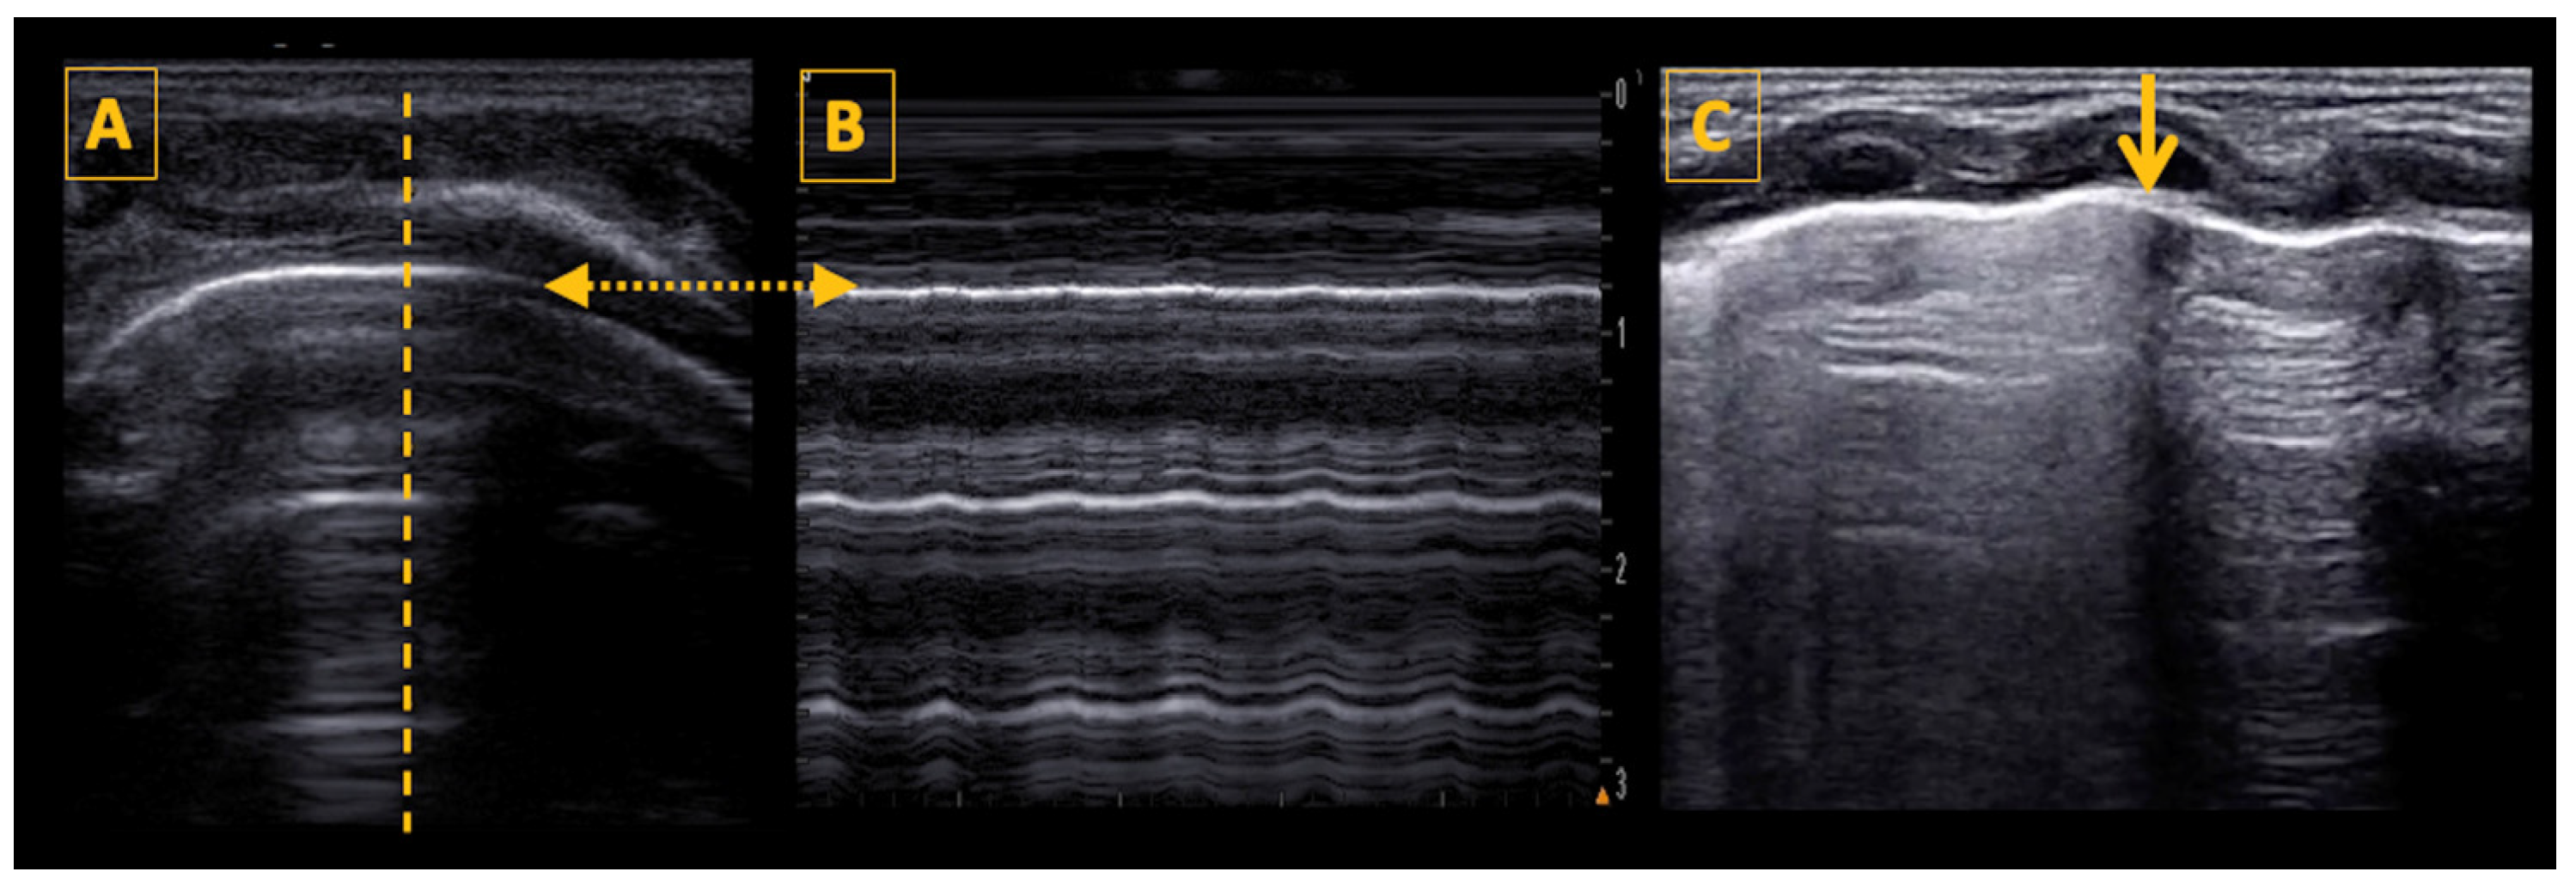

5.3. The Pleural Line, Lung Sliding, and the Lung Pulse

5.4. Lung Ultrasound Features and Signs

- Prada, G.; Vieillard-Baron, A.; Martin, A.K.; Hernandez, A.; Mookadam, F.; Ramakrishna, H.; Diaz-Gomez, J.L. Tracheal, Lung, and Diaphragmatic Applications of M-Mode Ultrasonography in Anesthesiology and Critical Care. J. Cardiothorac. Vasc. Anesth. 2021, 35, 310–322. [Google Scholar] [CrossRef]